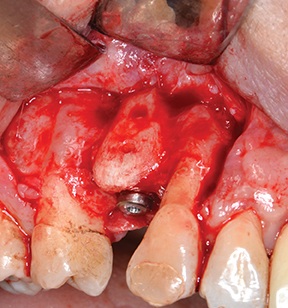

After a four-month healing period, a full-thickness flap was raised to evaluate the outcome (Fig. 21).

After removing fixation screws (Fig. 22), a 3.75 × 13 mm implant was placed with a final torque >35 N·cm (Figs. 23–24) and the flap was closed with 4-0 monofilament interrupted sutures (Fig. 25).

Fig. 21: Full-thickness flap raised at surgical re-entry

Block by Block

Fig. 22: Removal of fixation screws